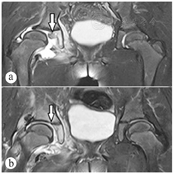

患儿,女,6岁9个月。因步态异常1个月余前来就诊。患儿1个月前摔倒后诉右侧腿痛伴跛行,无发热。查体:患儿跛行,双侧髋关节处未见明显皮肤缺损,右侧股动脉搏动不明显,右侧髋关节外展试验阳性,双下肢基本等长。实验室检查:血沉35 mm/h, C反应蛋白22 mg/L。CT检查示:右侧髋关节脱位,髋臼内形态不规则骨质密度影,血肿机化可疑。初步诊断:右侧感染性髋关节炎。入院后复查:血沉36 mm/h, C反应蛋白24 mg/L,外周血白细胞计数正常,T-spot结果正常,行髋关节穿刺2次,均未抽出液体。查3D-CT显示:右侧髋关节积液伴坐骨支髋臼面骨质异常,考虑感染及右髋关节半脱位。MRI显示:右侧髋关节积液伴周围软组织肿胀,右髋臼诸组成骨骨髓水肿,考虑感染;右髋臼缘下方见小骨片影,髋关节内侧间隙增大。予以抗感染(美洛西林钠舒巴坦钠1.5 g, 8 h 1次,五水头孢唑林钠0.5 g,8 h 1次)治疗1周后,症状无明显减轻,考虑患儿可能为幼年特发性关节炎,行抗CCP、抗"O"与RF、淋巴细胞免疫分析、体液免疫5项(IgA、IgG、IgM、C3、C4)、PCT等相关检查,结果均正常。再次行髋关节穿刺,抽出7 ml淡黄色液体,送检后无阳性结果。复查血沉36 mm/h, C反应蛋白正常。行髋关节穿刺,取黄色浑浊液体2 ml送细胞病理学检查,并查肿瘤4项(AFP、CEA、NSE、CA19-9),结果均正常。患儿经抗感染治疗28 d后,症状无好转,复查血沉28 mm/h。再次复查MRI,结果无明显改变,结合之前影像检查,诊断为:儿童髋关节剥脱性骨软骨炎,予以手术探查。术中发现右侧髋关节囊水肿明显,关节呈半脱位状态,关节内有约15 ml淡黄色清亮液体。髋臼内后方可见约0.5 cm×0.5 cm×0.5 cm大小软骨块突起于髋臼软骨表面,旁边可触及约1.0 cm×1.0 cm软骨面缺损。清除病灶后复位髋关节,术后髋上支架固定6周后脱架。术后病理报告:送检组织内可见增生的纤维组织、骨小梁、骨样组织,少量软骨及肉芽组织,其间见多量扩张的血管,局部伴出血,见慢性炎症浸润。结合影像学及临床表现符合儿童剥脱性骨软骨炎。术后患儿发热2 d,热峰38 ℃,C反应蛋白14 mg/L,血沉91 mm/h,予以对症处理后,均恢复正常,术后1个月患儿疼痛症状消失,复查CT、MRI等均见髋关节呈头臼同心圆结构,软组织肿胀消退(图1、图2)。予以出院,1年后随访患儿髋关节无不适,活动正常。

注:a术前,b术后。